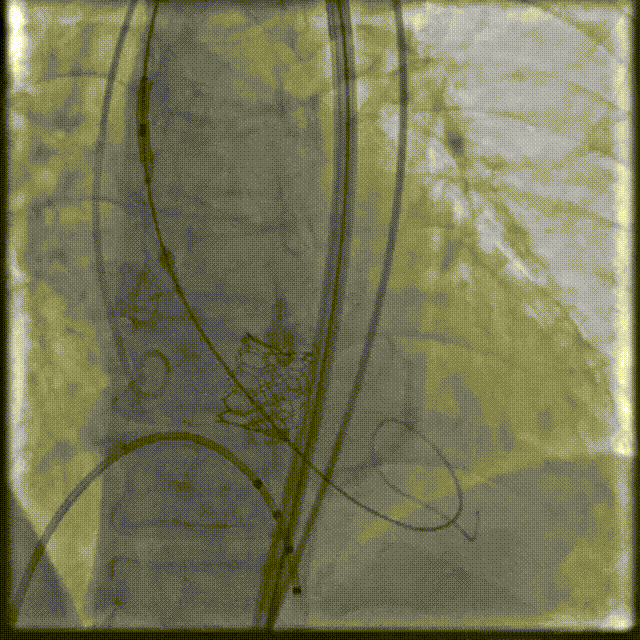

3.瓣膜输送到位,精准定位释放23 mm SAPIEN 3瓣膜。

4.术后即刻跨瓣峰值压差2mmHg,无反流。

图A、B 术前CT检查及术中影像均可见明显钙化团块(箭头所示),图C、D:球囊预扩张及人工瓣膜植入过程中均可见钙化团块明显移位(箭头所示)。

二叶瓣主动脉瓣狭窄解剖结构较为特殊,常合并主动脉瓣钙化、主动脉扩张等病变,导致TAVR术后易发生瓣周漏、瓣膜移位、瓣环破裂等多种并发症,TAVR操作具有一定挑战性。瓣膜尺寸选择及精确定位预防瓣膜发生滑脱方面需要认真考虑。二叶瓣瓣叶开口形态变化及瓣叶严重钙化使得实际瓣叶开口径通常小于瓣环径,瓣膜尺寸选择有时采用偏小型号(downsize策略),术前CT测量评估及术中球囊预扩张均可为瓣膜选择提供重要参考信息。尽管我们选取了偏小一号的23 mm SAPIEN 3瓣膜,在球囊预扩张及瓣膜植入过程中仍可以观察到钙化团块明显移位,如按照常规选择植入26 mm SAPIEN 3瓣膜会使瓣膜滑脱、瓣膜破裂等风险增加。该患者升主动脉明显增宽,会导致输送系统过弓后向大弯侧移位,再加上主动脉瓣钙化严重,从而进一步增加了跨瓣的难度,SAPIEN 3瓣膜经导管主动脉瓣瓣膜输送系统具有双重调弯功能,可调节远端辅助通过复杂的解剖结构,降低主动脉损伤的风险,并有助于瓣膜定位过程中控制同轴性,精细控制定位,确保精准放置人工瓣膜。术后患者恢复良好,胸闷、气喘症状消失,心功能明显改善,顺利出院。